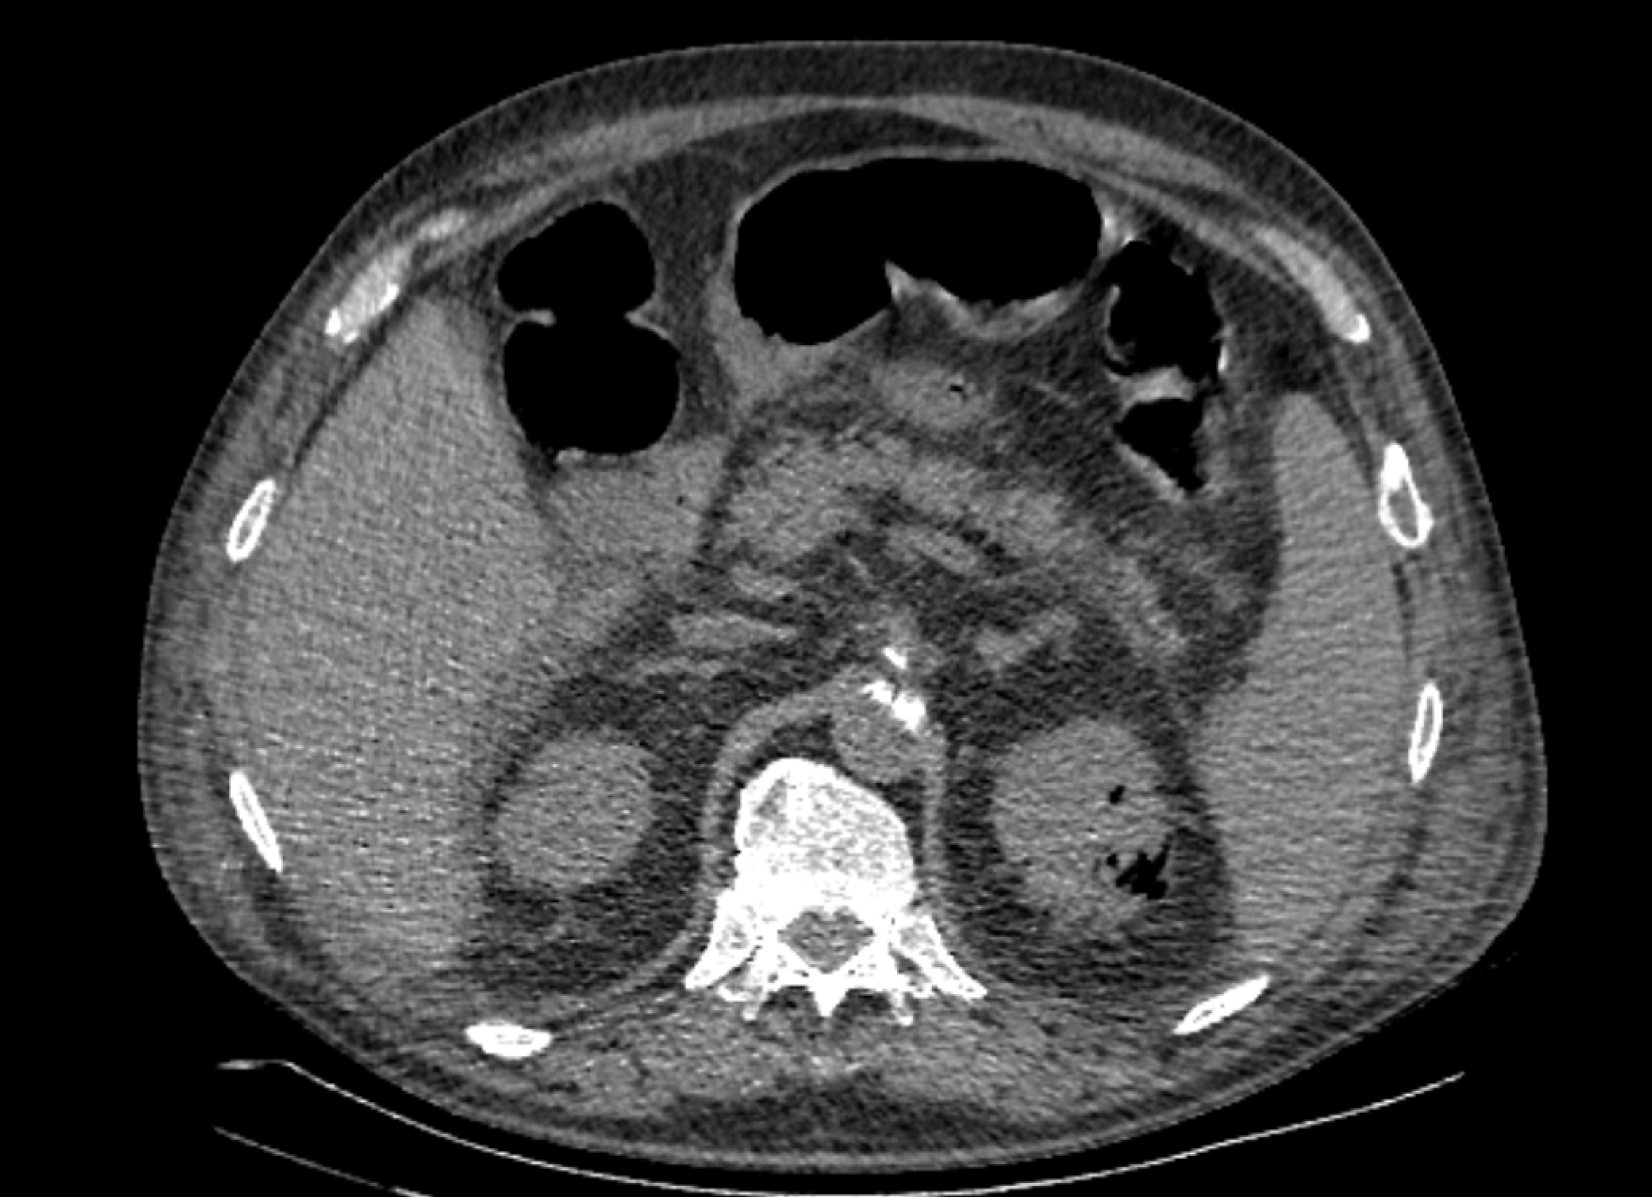

На следующий день состояние пациента оставалось тяжелым, с отрицательной динамикой, креатинин сыворотки возрос до 735,2 ммоль/л, Появились жалобы на слабость, тошноту. При осмотре: живот мягкий, вздут по всем отделам, при пальпации болезненный. Область почек не изменена, при пальпации безболезненна, патологических изменений в области почек не выявлено. Симптом поколачивания отрицательный билатерально. При УЗИ были обнаружены плевральный выпот по 300–400 мл с каждой стороны, гепатомегалия, увеличение размеров селезенки, асцит. Кроме того, в обеих почках были визуализированы тени, характерные для конкрементов. По данным компьютерной томографии (КТ) конкрементов не обнаружено, но в лоханке, на всем протяжении левого мочеточника и, частично, в правом мочеточнике, а также в мочевом пузыре визуализировался газ (рис. 1–6).

Рис. 1. Компьютерная томография органов брюшной полости, забрюшинного пространства, органов малого таза. Газ в мочевом пузыре

Рис. 2. Компьютерная томография органов брюшной полости, забрюшинного пространства, органов малого таза. Газ в мочевом пузыре

Рис. 4. Компьютерная томография органов брюшной полости, забрюшинного пространства, органов малого таза. Газ в почках